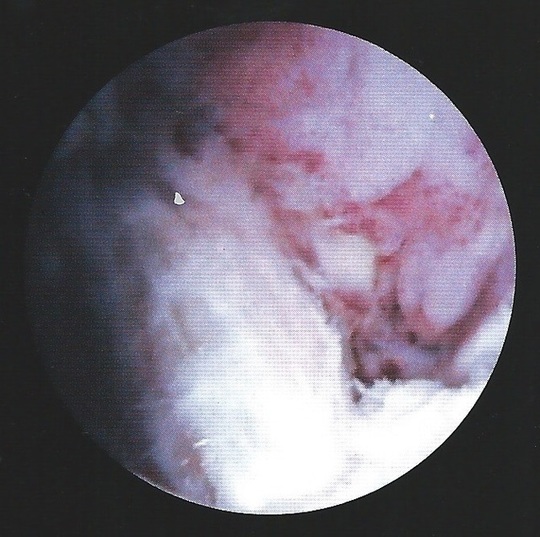

膝にたまった血液を抜いているところ